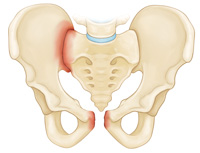

Superior and inferior pubic ramus fracture

Anterior-posterior compression fracture

Lateral compression fracture. In this fracture, the pelvis is pushed inward.

The pelvis helps anchor the muscles and protect the organs in the lower abdomen.